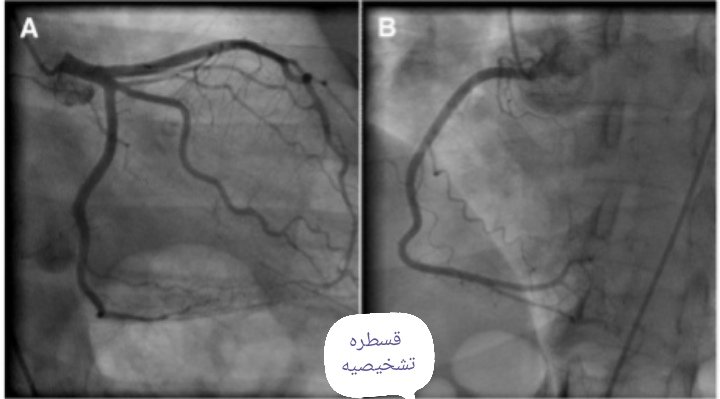

وعند وصول القسطره (الأنبوب) إلى القلب يتم حقن الشرايين بالصبغه حتى يتسنى للطبيب مشاهدة الشرايين.. ومن ثم يتم تحديد ما اذا كان هناك ضيق بالشرايين (إلى هنا تسمى قسطره تشخيصيه) ... فإذا لم يكن هناك ضيق تنتهى القسطره... أما إذا هناك ضيق فهناك عدة احتمالات( 2/3)

منها ان يكون هناك ضيق ممكن علاجه بوضع دعامات او عدة تضيقات ومعقده يتم تحويل المريض إلى الجراحه.. وهناك احتمال ان يكون الشريان بوضع لايسمح عمل اي شي سوى العلاجات..معلومه مهمه سبل العلاج تتم عن طريق توصيات معتمده يتبعها الطبيب.. اللهم اشفى كل مريض..